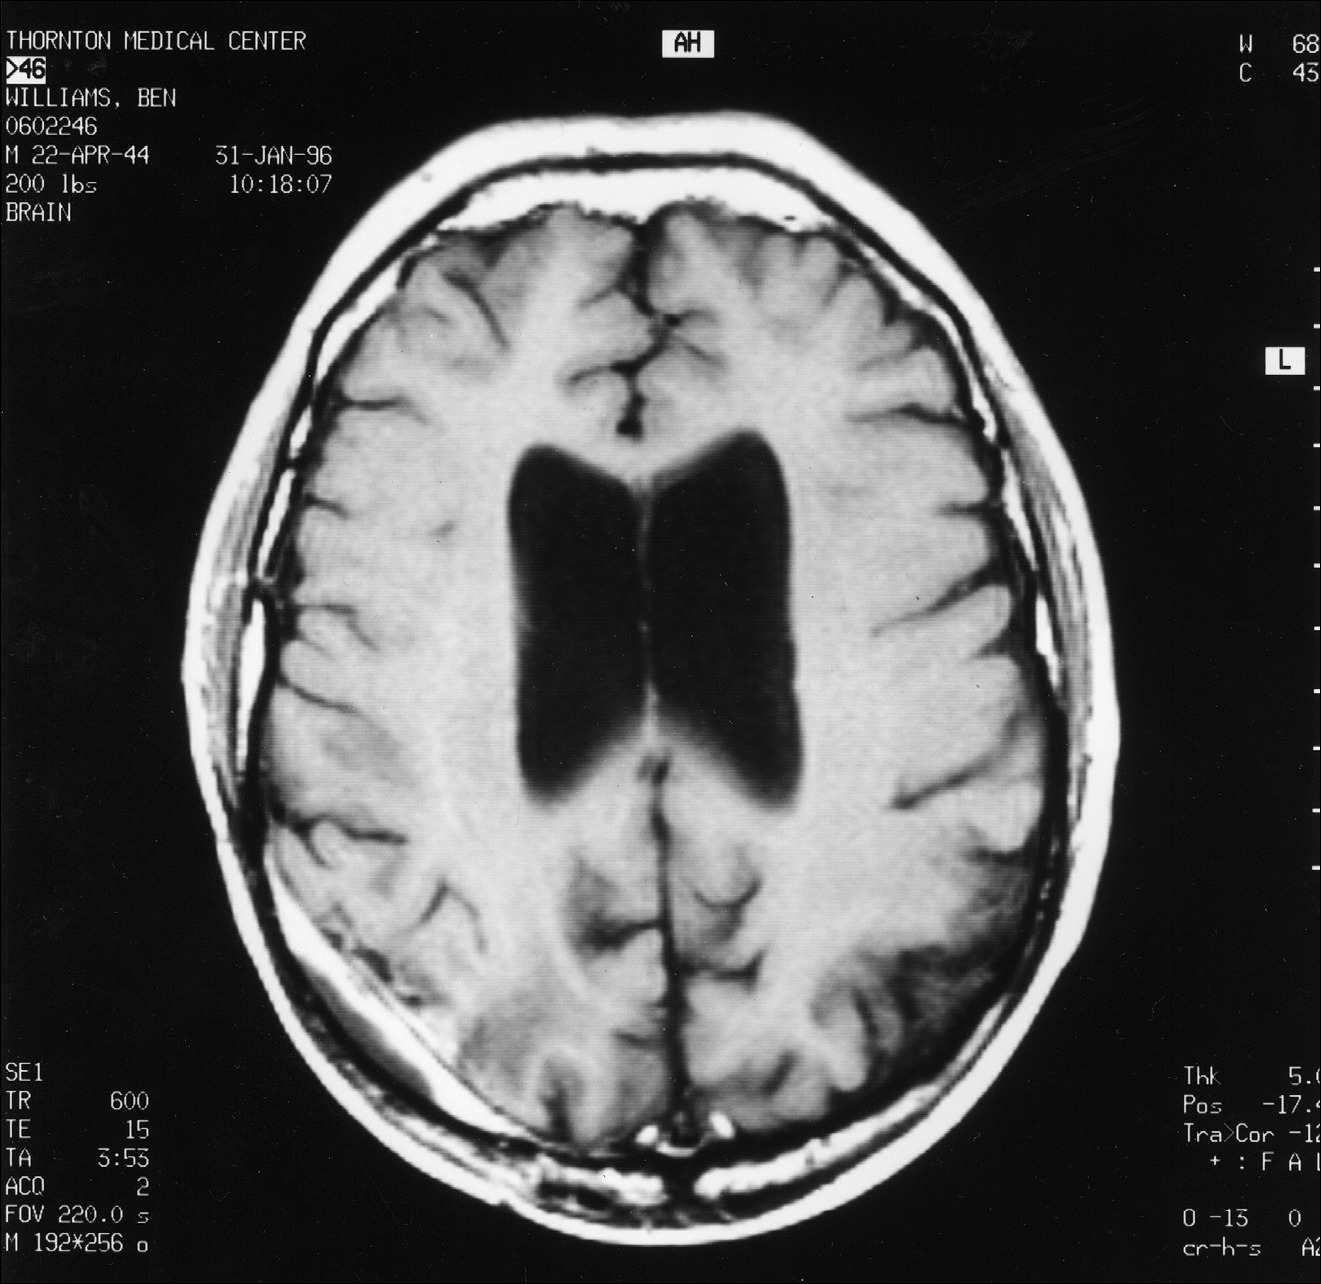

5 pav.

MRT pjūvis, atitinkantis pjūvius, parodytus 1 pav. ir 3 pav.

6 pav.

MRT pjūvis, atitinkantis pjūvius, parodytus 2 pav. ir 4 pav. Nors vis dar matomas nedidelis paryškinimas, jis atrodo esąs palei kietąjį dangalą, o ne žievėje.